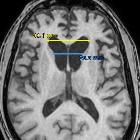

Frontal horn width to intercaudate distance ratio (FH/CC) is used in assessing patients with suspected Huntington disease. An alternative measurement is intercaudate distance to inner table width ratio (CC/IT).

On the same axial plane obtained on the ACPC (anterior commissure and posterior commissure) line, the ratio between the lateral margins of the frontal horns and the distance between the caudate heads (where they are closest).

The normal mean FH/CC ratio range is 2.2 to 2.6. As the caudate heads reduce in volume the CC distance will approach the FH distance, and the ratio will approach 1.